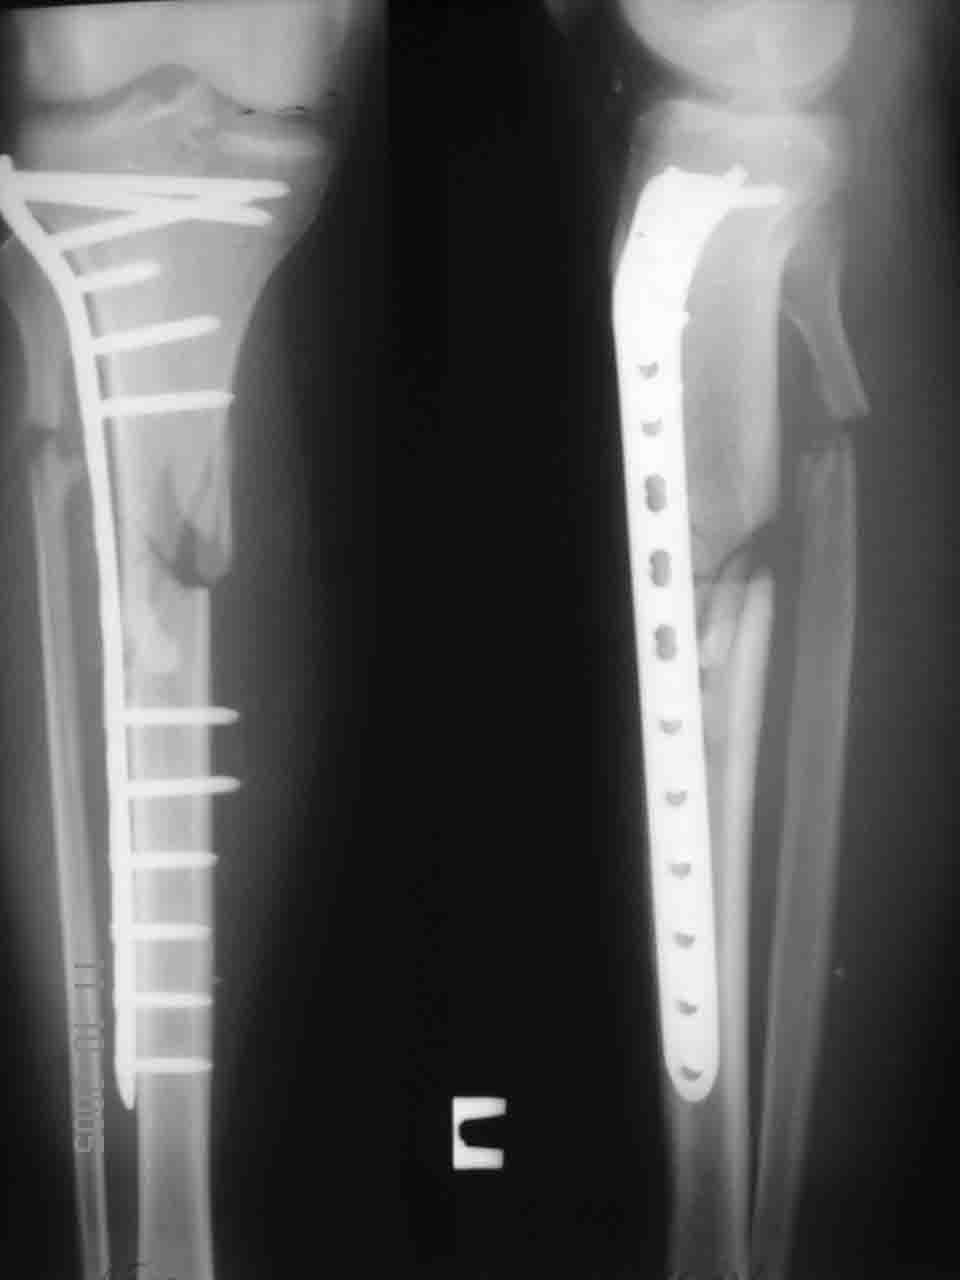

Несращение tibia с LCP

Уважаемые коллеги! 2,5 месяца назад в нашем отделении прооперирован больной 30 лет. Закрытые переломы голеней справа - в/3 слева - ср/3.

Слева был выполнен интрамедуллярный остеосинтез UTN, справа пластиной LCP. Через два месяца разрешили ходить при помощи костылей с преимущественной нагрузкой на левую ногу. Произошел перелом пластины. Планируем удалить пластину и наложить аппарат Илизарова, также рассматривали вариант интрамедуллярного остеосинтеза. Ваше мнение? С уважением, Алексей Смирнов.